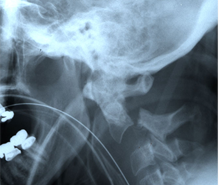

Spinal Trauma and Fractures

Spinal injuries can be serious life threatening problems that cause paralysis requiring complex surgical repair and others are lesser injuries that my only result in transient pain that are treated with a brace or collar while they heal. Fractures can occur in various regions of the spine and must be evaluated by a spine surgeon with experience in these injuries.